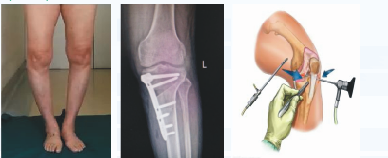

骨关节炎疼痛阶梯治疗(关节镜检查治疗、胫骨截骨矫形保膝)

关节炎临床表现红、肿、热、痛、功能障碍及关节畸形。治疗遵循“金字塔诊疗模式”,个体化定制治疗方案。尤其擅长对髋、膝骨性关节炎疼痛阶梯治疗。

中期治疗:采用氨基葡萄糖或注射玻璃酸钠、富血小板血浆(PRP)等辅助治疗,增加软骨营养,促进损伤修复,严重者可进行截骨矫形(HTO)、关节镜微创。

胫骨截骨矫形(HTO):矫正膝内外翻畸形,避免胫骨和股骨关节软骨摩擦而引发的疼痛,降低胫骨内压、改善关节功能、减轻疼痛,延缓关节炎进展,使蜕变的关节软骨得到部分修复,从而使临床症状消失或减轻,避免关节置换术。关节镜优点:切口小、创伤小、瘢痕小、康复快、并发症少。